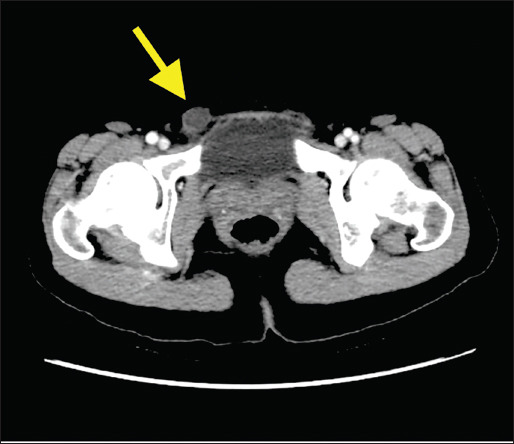

Case report: A 43-year-old female patient, presented to our hospital with a five-year history of swelling and slight discomfort in the right groin. A nonreducible inguinal mass with greater projection during a Valsalva maneuver was found. An abdominal CT scan revealed a well-defined lesion located near the right horn of the uterus and extending through the inguinal canal. The patient was brought to the operating room with the clinical suspicion of an inguinal hernia. A soft mass measuring 4.5×2×1.8cm was discovered in the right round ligament, and it was surgically removed. Histopathological examination confirmed a mesothelial cystic lesion. The patient's condition, after a period of 12 months, continues to be satisfactory.